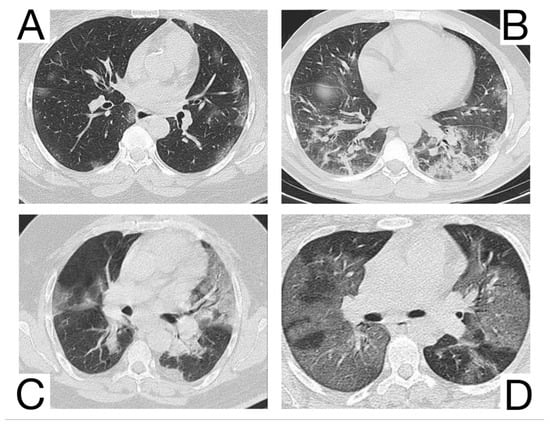

10.12. Differential Diagnosis between COVID-19 Pneumonia and Idiopathic Interstitial Pneumonia (IIP)

COVID-19 pneumonia and IIP represent complex pulmonary pathologies, and the differential diagnosis is frequently challenging.

The radiological and tomographic aspects must always be correlated with the anamnesis, clinical, and laboratory data.

Idiopathic interstitial types of pneumonia and COVID-19 pneumonia are different entities but share some similar radiological features.

The association between typical symptoms and correlated radiological images can suggest the diagnosis of COVID-19 and warrant the isolation of patients to avoid the spread of infection [].

Yet, a discordance between the patients’ anamnesis and the imaging should suggest a possible differential diagnosis [,]. Comparison with previous CT scans is crucial to identify possible chronic or long-standing radiological findings of IIP. In general, the presence of typical and/or additional radiological changes that are less frequent or rare in COVID-19 pneumonia is found in IIP (Figure 13A,B) [,]: the migration of condensation foci (organizing pneumonia); preferential involvement of the lobular periphery, resulting in a “peri-lobular pattern” (pneumonia in organization); ground glass opacities during disease exacerbation; relative reduction of the subpleural lung tissue (nonspecific interstitial pneumonitis, organizing pneumonitis); predominance in the upper fields (bronchiolitis associated with interstitial lung disease, lymphoid interstitial pneumonia, pleuropulmonary fibroelastosis) []; apicobasal gradient and heterogeneous lung involvement (idiopathic pulmonary fibrosis); clear demarcation between the healthy lung parenchyma and the affected parenchyma (idiopathic pulmonary fibrosis) []; the coexistence of other radiological findings such as centrolobular nodules (bronchiolitis associated with interstitial lung disease, organizing pneumonia) and thin-walled cysts (interstitial lymphoid pneumonia) []; the presence of fibrosis that can be appreciated as parenchymal distortion, bronchial traction, and/or honeycombing (idiopathic pulmonary fibrosis, nonspecific interstitial pneumonitis); pleural thickening (pleuropulmonary fibroelastosis); pleural effusions (exudative acute interstitial pneumonia, organizing pneumonia).

Figure 13. Idiopathic interstitial pneumonia (A,B). Bilateral septal thickening and honeycombing with more severe involvement toward the lung bases. Note. Case courtesy of Dr. Hani Makky Al Salam, Radiopaedia.org, rID: 41974.

The differential diagnosis of COVID-19 pneumonia with IIP is challenging because these entities may share common radiological aspects. Therefore, a multidisciplinary approach is crucial to arrive at a final and correct diagnosis [,].